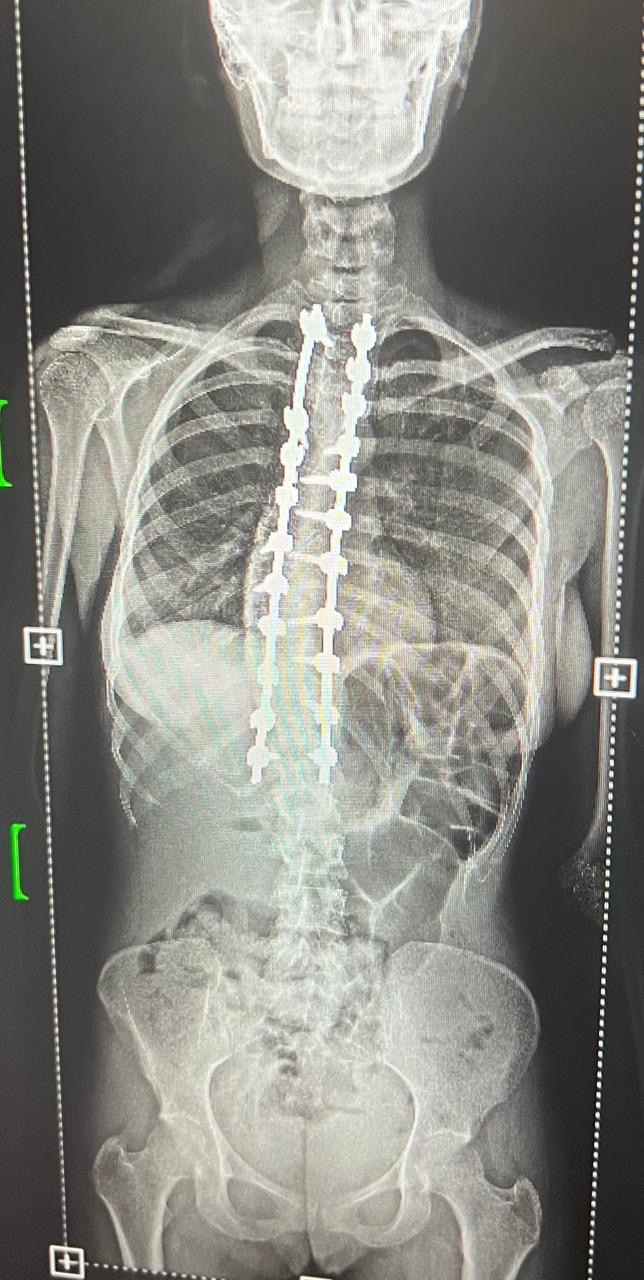

وخضعت الحالتان لتقييم طبي شامل ودقيق تضمن إجراء كافة الفحوصات الإكلينيكية والأشعة المتخصصة، التي كشفت عن وجود تشوهات ودرجات انحناء متقدمة استوجبت التدخل الجراحي العاجل لتفادي المضاعفات.

واستعان الفريق الطبي بأحدث التقنيات العالمية في هذا المجال، معتمداً بشكل أساسي على أجهزة المراقبة العصبية الدقيقة لضمان أعلى معايير الأمان وسلامة الأعصاب الحساسة أثناء إجراء التعديل.

واستغرقت كل عملية نحو ثماني ساعات متواصلة من العمل الدقيق، نظراً لتعقيد الحالات وحاجتها لتنسيق عالٍ ولحظي بين جراحي العمود الفقري وفريق التخدير لضمان استقرار المريض.